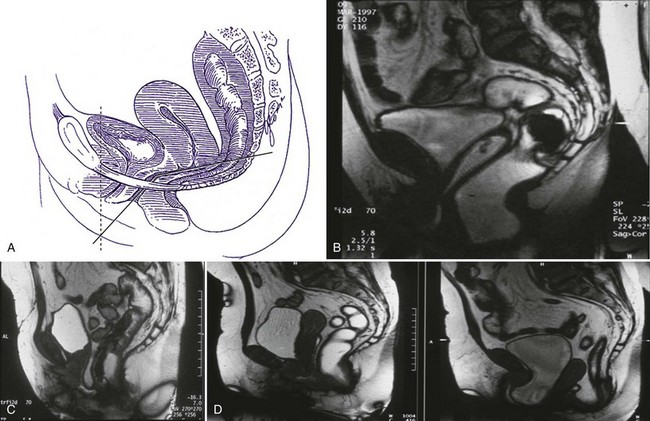

Berglas and Rubin (1953) showed that in the nulliparous patient, the lower one third of the vagina is oriented more vertically, while the upper two thirds deviate horizontally, thereby maintaining the vaginal axis in an almost horizontal position (Fig. 63–5A and B). This configuration is maintained by the posterior attachments of the cervix with the cardinal and utero-sacral ligaments and by the anterior position of the urogenital hiatus. During stressful maneuvers such as coughing or straining, the levator hiatus is shortened anteriorly by contraction of the pubococcygeus muscles (Fig. 63–5C). In the case of genital prolapse when the levator ani support is lost, the vaginal axis becomes more vertical, the urogenital hiatus broadens, and fascial supports are strained (Fig. 63–5D).

Figure 63–5 A, In the nulliparous patient, the lower one third of the vagina is oriented more vertically, whereas the upper two thirds deviate horizontally, thereby maintaining the vaginal axis in an almost horizontal position. B, In the nulliparous patient, the lower one third of the vagina is oriented more vertically, whereas the upper two thirds deviate horizontally, thereby maintaining the vaginal axis in an almost horizontal position. C, During stressful maneuvers such as coughing or straining, the levator hiatus is shortened anteriorly by contraction of the pubococcygeus muscles. D, In the case of genital prolapse when the levator ani support is lost, the vaginal axis becomes more vertical, the urogenital hiatus broadens, and fascial supports are strained.